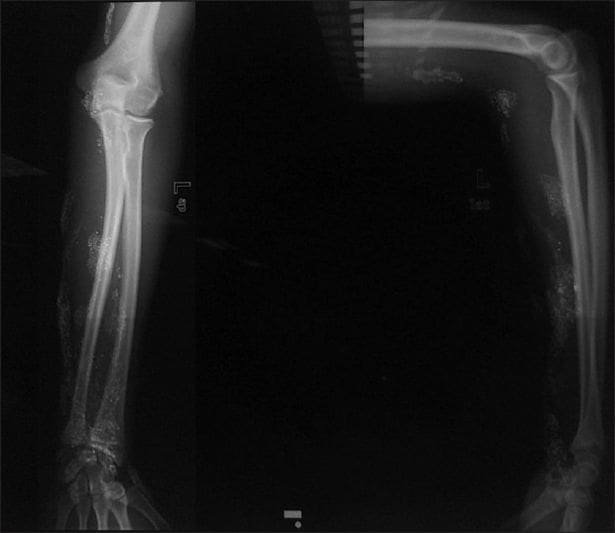

Y es que, en su afán de ser superhéroe de Marvel, este adolescente sacó mercurio de un termómetro casero y con una jeringa, se lo inyectó en el brazo vía subcutánea.

Como era de esperarse, la piel del joven reaccionó al estar en contacto con la sustancia tóxica para el cuerpo humano. Esto le ocasionó una úlcera que no cicatrizó.

“Se realizó un procedimiento quirúrgico para tratar la úlcera y reducir los niveles de mercurio en sangre y orina," se explicó en el informe.

Aunque se agregó que el paciente no desarrolló signos clínicos de intoxicación crónica:

"Sin embargo, el paciente no desarrolló signos clínicos de intoxicación crónica, lo que demuestra que la inyección subcutánea de mercurio tiene un riesgo bajo de toxicidad sistémica”, se explicó en el informe.